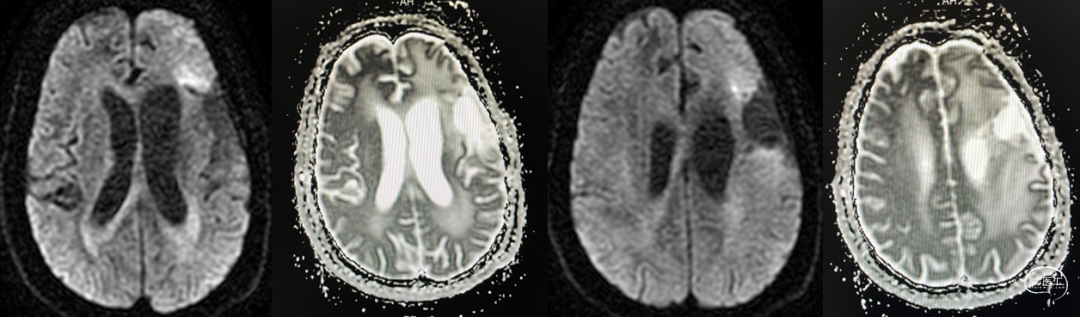

放疗后17月(2021-12-20)MRS显示左颞叶感兴趣区Cho/NAA约1.19-5.53:图示。

术后5周开始实施标准的新STUPP方案的辅助治疗,即在同步放化疗后,辅助替莫唑胺化疗的同时使用了电场治疗。目前生存25月,且临床和影像学表现均提示稳定,未见复发迹象。期间,在放疗后7月时复查MRI提示异常FLAIR信号区增大,经我院MDT讨论,考虑到强化信号减轻,无明显占位效应,患者无症状体征,考虑是治疗后水肿,非进展,故继续按原方案治疗。放疗后17月复查MRI出现术区边缘局部强化范围稍增大,但PWI示强化区局部呈低灌注且未见弥散受限表现,MDT讨论考虑为假性进展,继续原方案治疗。后续复查MRI强化范围减轻,证实了MDT的判断证实疾病稳定。患者生存时间已达25个月。全程安全顺利,仅出现一过性轻度皮肤反应。

辅助TMZ治疗过程中每2-3月复查MRI。治疗中曾出现水肿范围增大,尽管有部分区域弥散受限和MRS异常及血流量增加,但是临床症状未加重,仍继续原方案治疗,后续监测PWI显示病变区灌注减低。提示持续肿瘤电场治疗可以使病变长期稳定。此患者每天佩戴肿瘤电场治疗时间接近22小时,中间出现头皮发红和小水泡,经局部外用皮质类固醇和外用抗生素,暂停2天治疗恢复。至今随访25月稳定。说明肿瘤电场治疗联合TMZ治疗较单TMZ治疗明显延长胶质母细胞瘤患者PFS及OS,临床应积极推广使用。